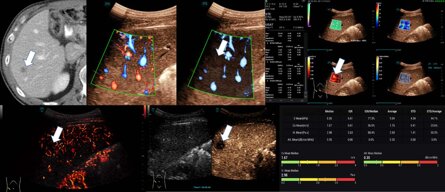

STVi consente la valutazione quantitativa della viscosità dei tessuti e fornisce immagini multiparametriche in tempo reale, offrendo un approccio più completo alla diagnosi per immagini e all'analisi quantitativa di malattie epatiche croniche, lesioni mammarie e altre condizioni.

M Reference è uno strumento di analisi combinata multiparametrica che consente diagnosi MPUS in tempo reale, nella stessa sezione e nella stessa schermata. A differenza delle tradizionali immagini ecografiche singole, offre informazioni diagnostiche multidimensionali e indicatori di valutazione quantitativa per le malattie.

Tutti gli esami sono stati eseguiti da un esaminatore esperto (>3000 esami/anno, >20 anni)

utilizzando un ecografo di fascia alta (Mindray/Resona A20) con una sonda convessa da 1 a 7 MHz

(SC7-1M). Le richieste di esami ecografici sono state effettuate in base alle decisioni del comitato oncologico. Il consenso informato scritto era disponibile per gli esami CEUS in tutti i casi. La diagnostica epatica CEUS

è conforme alle linee guida EFSUM come uso on-label [3]. È disponibile un voto etico positivo del comitato etico locale (come parti dello studio DEGUM IV) [5].